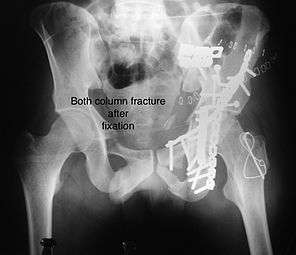

Combined both column fractures

These are the most complex injuries. Here the weight bearing roof or dome of the acetabulum is a floating piece. This adds to complexity of management.

How to diagnose: all three x-ray views plus CT scan is a must for diagnosis and management of this complex injury

Surgical management is ideal. The choice of approach rests with the surgeon, but going from front, or anterior approach is preferred. The posterior injury may be tacked with anterior approach by experienced surgeon.